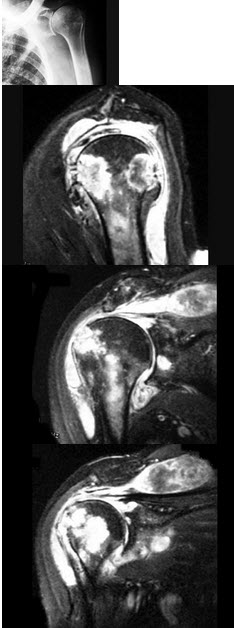

146、单项选择题

女,71岁,左肩痛,系统性红斑狼疮服用高剂量的类固醇半年,结合图像,最可能的诊断是()

A.化脓性关节炎

B.类风湿关节炎

C.骨纤维肉瘤

D.肱骨头缺血坏死

E.肩关节结核